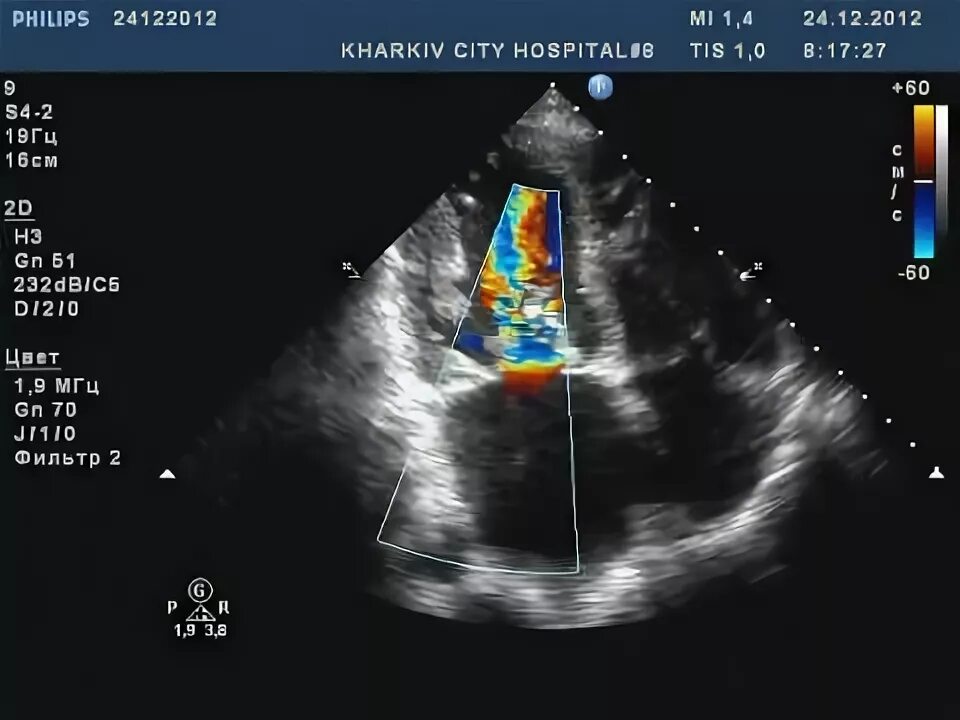

Частичный отрыв